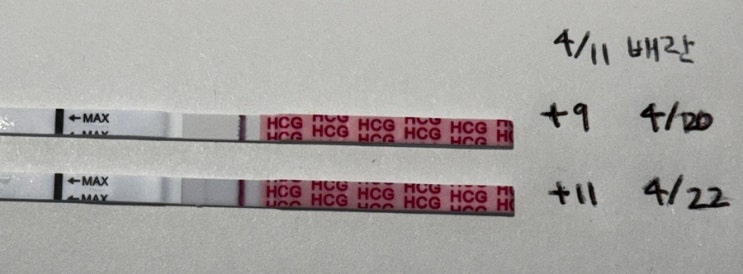

임신준비이야기 - 배란 1일차부터 배란 9일차, 배란 11일차까지 증상 및 임테기

지난 글에 나와있듯이 나는 배란유도제 페마라를 5일동안 2정씩 복용했고 배란 초음파를 통해 1개의 난포가...